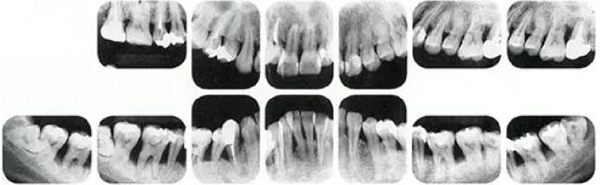

①的患者是35歲女性。4~10mm的牙周袋和大量的牙石。特別是在左上、右下、左下的磨牙處能看到大量牙槽骨吸收。這名患者是慢性牙周炎,僅在磨牙處有局部由風(fēng)險(xiǎn)因子導(dǎo)致(解剖學(xué)形態(tài))導(dǎo)致的重度病癥發(fā)展。

②將會(huì)是什么樣的呢?左上、右下、左下的磨牙處有大量牙槽骨吸收,考慮到其發(fā)病年齡,斷定為是侵襲性牙周炎局部型。

但是實(shí)際上參考病例①和②是同名患者,①是②10年后的狀態(tài)。這名患者間隔10年后來(lái)就診,讓我們可以確認(rèn)到癥狀的變化。

●參考病例① 35歲女性

35歲女性。妊娠4個(gè)月。過(guò)去雖然接受過(guò)刷牙指導(dǎo),但菌斑控制狀態(tài)依然不理想?;颊哂邪l(fā)現(xiàn)自己刷牙時(shí)牙齦出血。

●參考病例② 25歲女性

25歲女性。菌斑控制狀態(tài)不好。齦溝除磨牙處外全在3mm以下,X光照片上左上、右下、左下的第一磨牙上有垂直性骨吸收。這個(gè)病例是參考病例①10年前的狀態(tài),是典型的侵襲性牙周炎局部型。